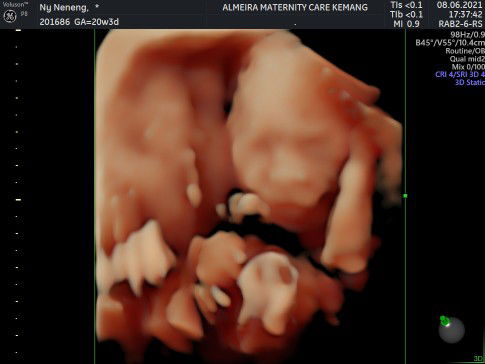

Penyebab Janin Bergerak Terasa Sampai Miss V dan Tips Mengatasinya

Semakin besar kehamilan mungkin Bunda akan semakin sering merasakan gerakan janin. Bahkan pada trimester ketiga, Bunda bisa merasakan janin bergerak terasa sampai miss V. Kondisi ini normal nggak ya? Sebaiknya cek penyebab dan cara mengatasinya di sini: https://id.theasianparent.com/janin-bergerak-terasa-sampai-miss-v/web-view/?pinned=post Share di kolom komentar, apakah Bunda sedang atau pernah mengalami ini?